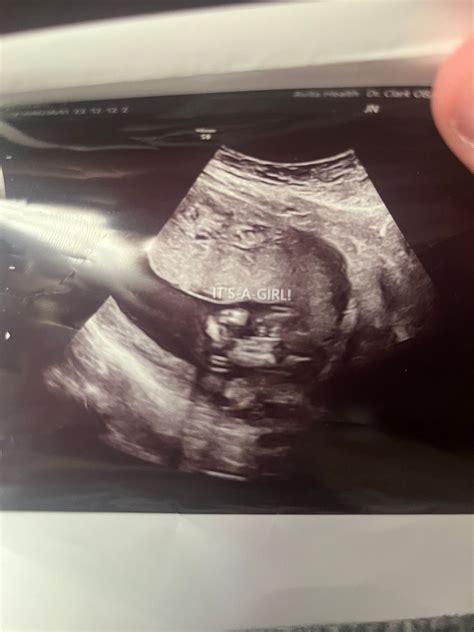

16 Weeks Pregnant Ultrasound

At 16 workweek, you are formally in your quaternary month of pregnancy. Your baby is grow rapidly, and your body is undergoing numerous alteration to back this growth. This workweek is oft tag by a routine prenatal check-up, which may include a 16 weeks meaning ultrasound. This echography is typically perform to value your baby's ontogeny and to insure for any likely matter.

At 16 week, you are well on your way to welcome your little one into the world. The 16 weeks significant ultrasound is a important milepost that provides valuable insights into your baby's growth and overall health. Embracing this journeying with fervor and self-confidence, know that you are rear a new life with love and fear.

• 16 weeks pregnant ultrasound sex

• 16 hebdomad daughter ultrasound icon